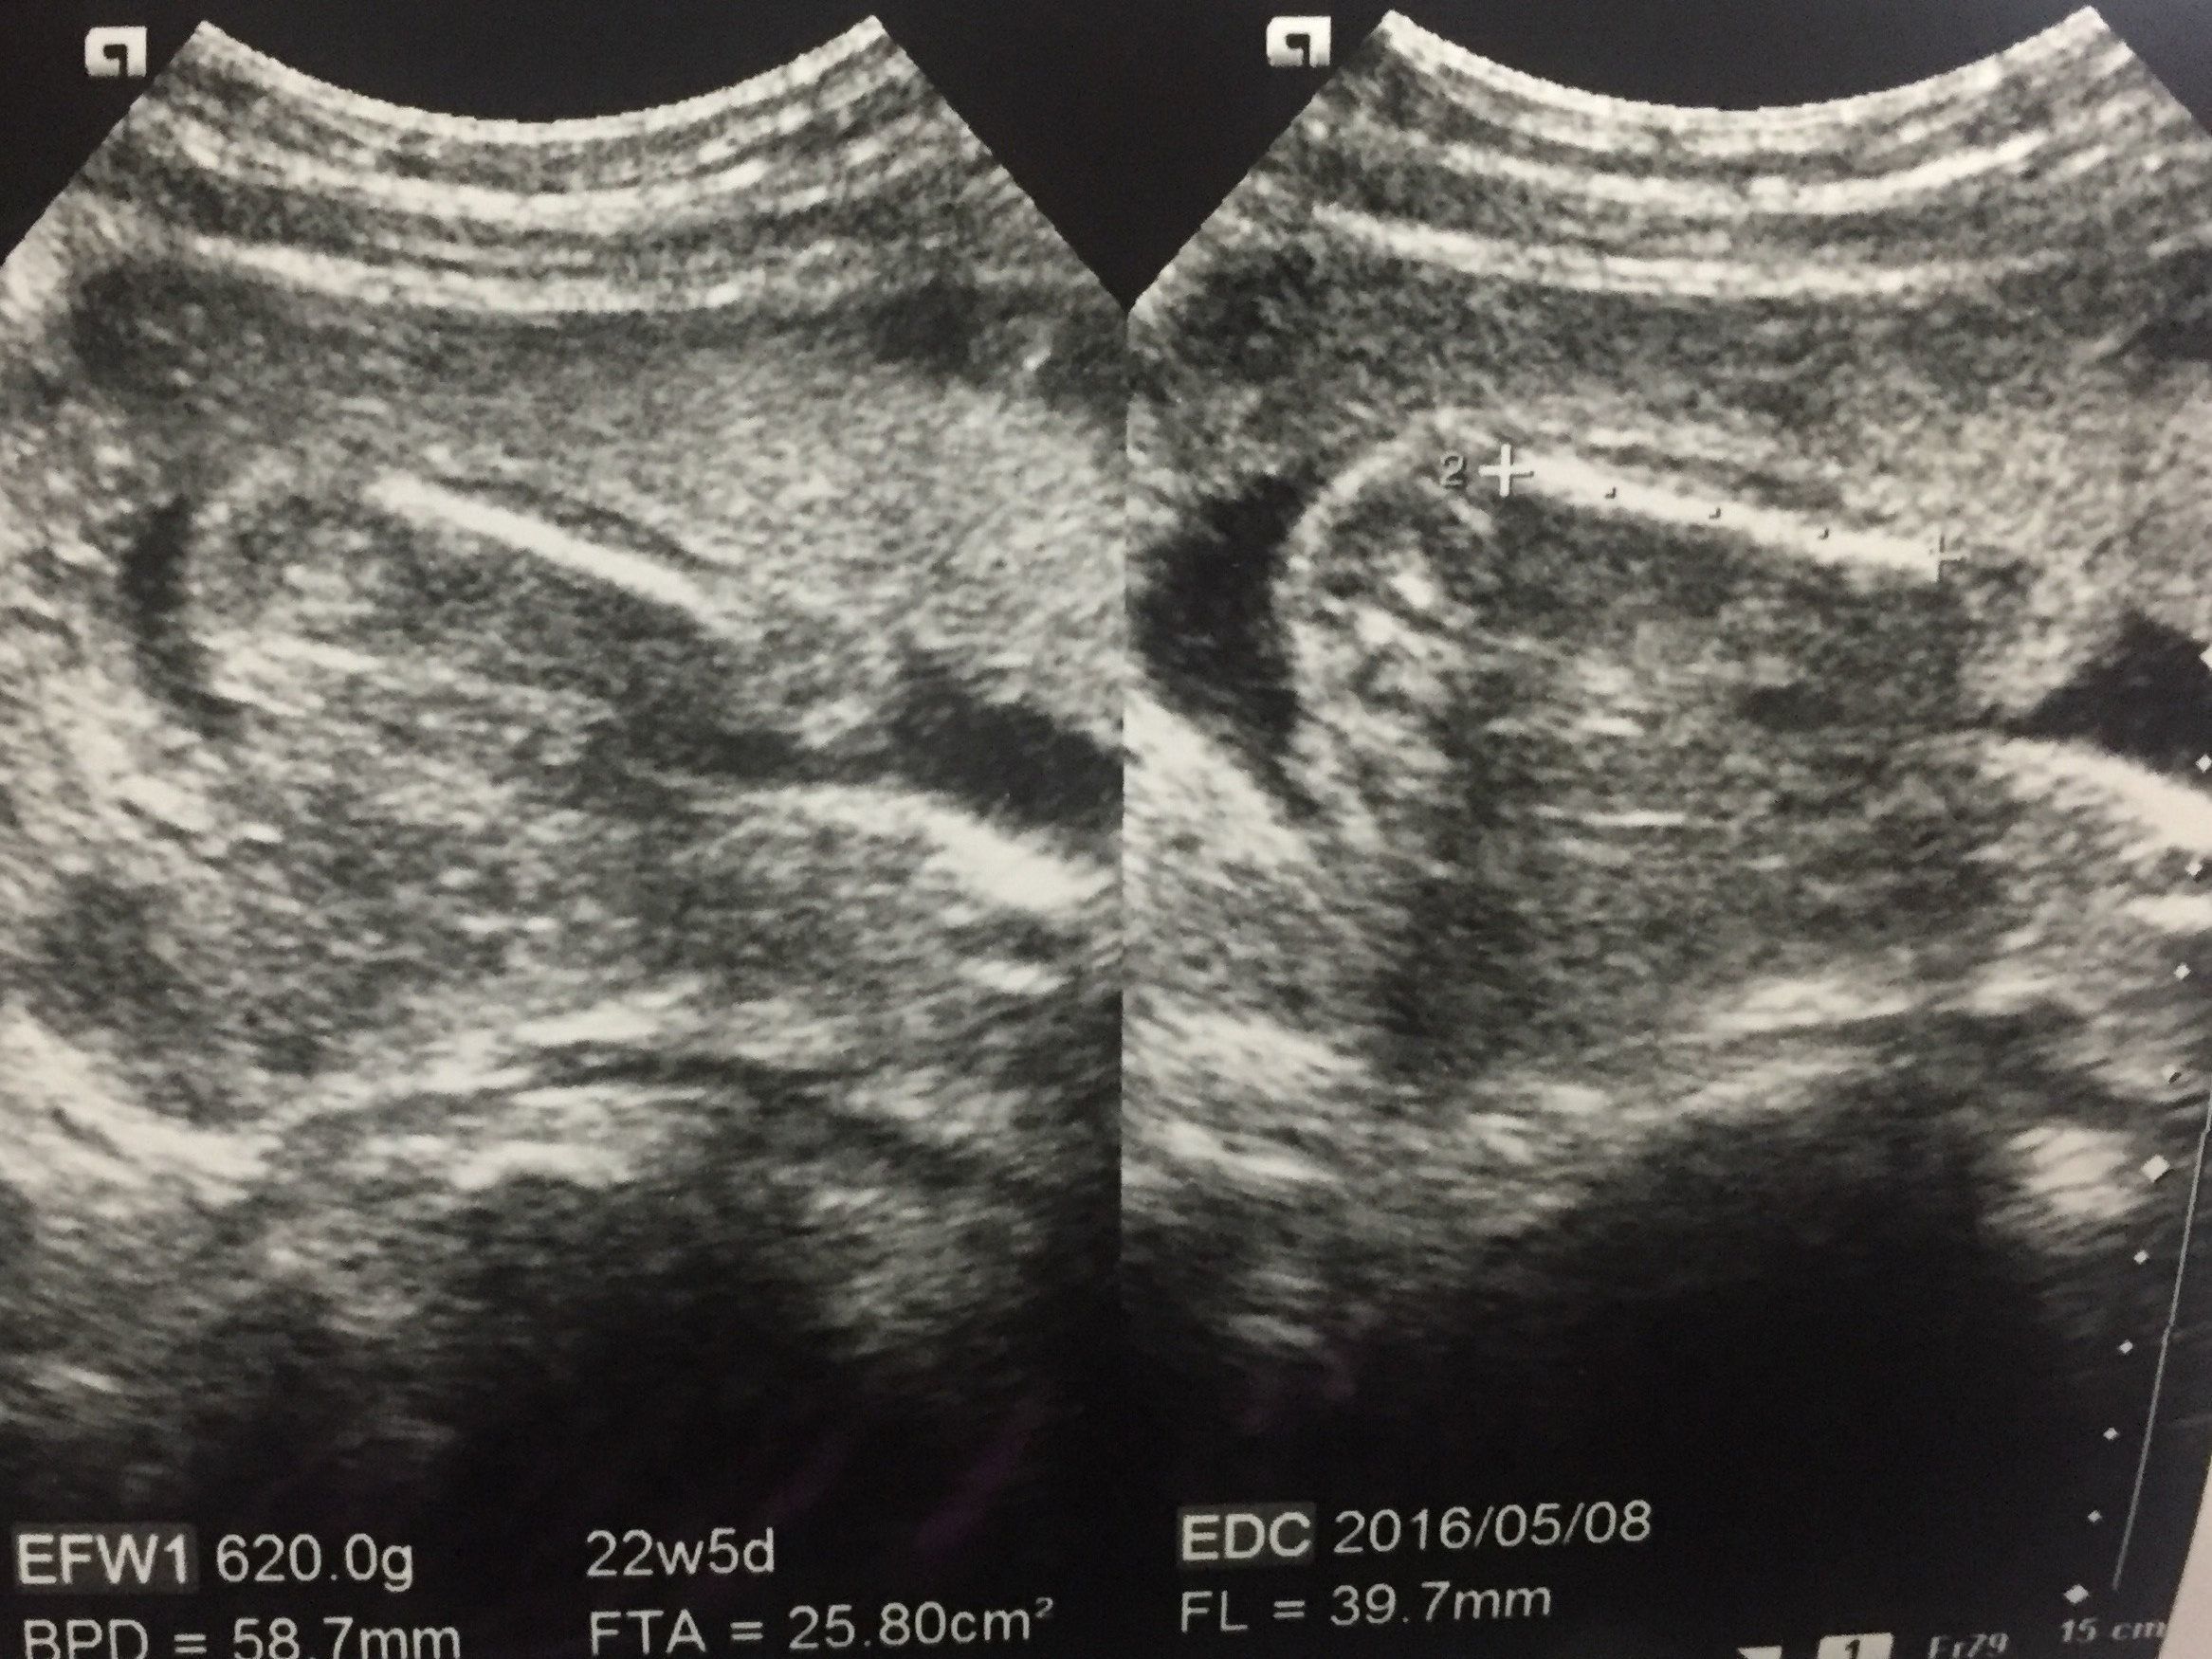

妊娠22週目 胎動が感じられるようになり、安心で幸せ

この写真も赤ちゃんをお尻側から撮影したもので、右の方に足が2本伸びています。足と足の間を見ると、男の子だろうということがわかります。

毎日胎動を感じるたびに「赤ちゃんが元気でいてくれている」と自分で確認ができ、安心で幸せな気持ちでした。

性別もわかり、どんな名前にしようかと夫と相談を始めました。買うべき赤ちゃん用品をリサーチするのも楽しかったです。